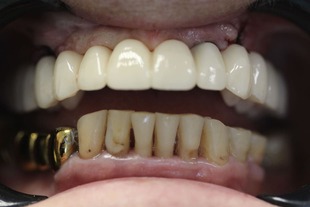

До

После

Неравномерная патологическая стираемость зубов. Установлены импланты в боковых отделах верху и внизу. Протезирование на имплантах циркониевыми коронками+ виниры на передние зубы.